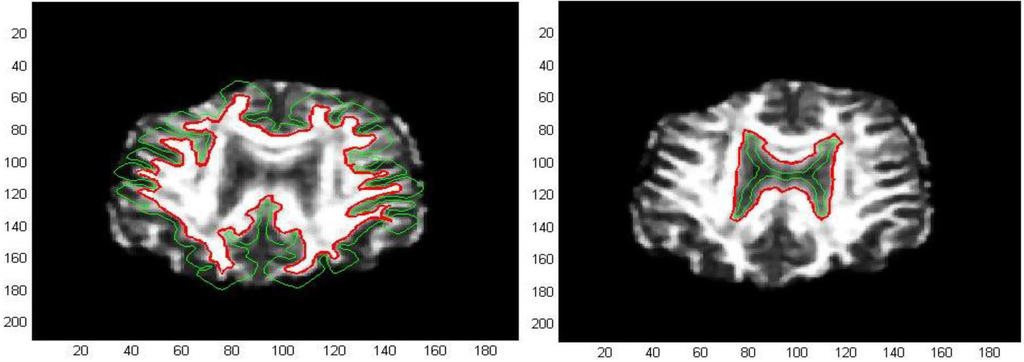

The first processed GM image (Figure 11) refers to a subject of the control group (see the first image of Figure 12). The force field has been evaluated from Equation (9) after eight iterations, the overlapping green curves represent initial contours that are automatically selected from the contour map of divergence. In Figure 13 and Figure 14 we have treated GM images derived from two patients affected by Alzheimer’s disease and they refer respectively to the second and third images which are shown in Figure 12. Once edges are detected, we produce a boundary representation of gray matter that can be used for an automatic analysis of shapes from the geometrical, metrical or morphological point of view.

Figure 11. Edge extraction with AVF force field after 8 iterations.

Figure 12. GM images for a subject of the control group and two patients affected by Alzheimer’s disease.

Figure 13. Edge extraction with AVF force field after 8 iterations.

Figure 14. Edge extraction with AVF force field after 8 iterations.

Moreover, we test the AVF method with T1-weighted MRI images of our dataset. The initial positions of the active contours are shown in green overlaid on the real image, whereas the outlines of the final contours are drawn in red. Many details of borders are captured both for gray matter and lateral ventricle profiles, whereas the interhemispheric fissure contours results are not completely retrieved, as we can see in Figure 15.